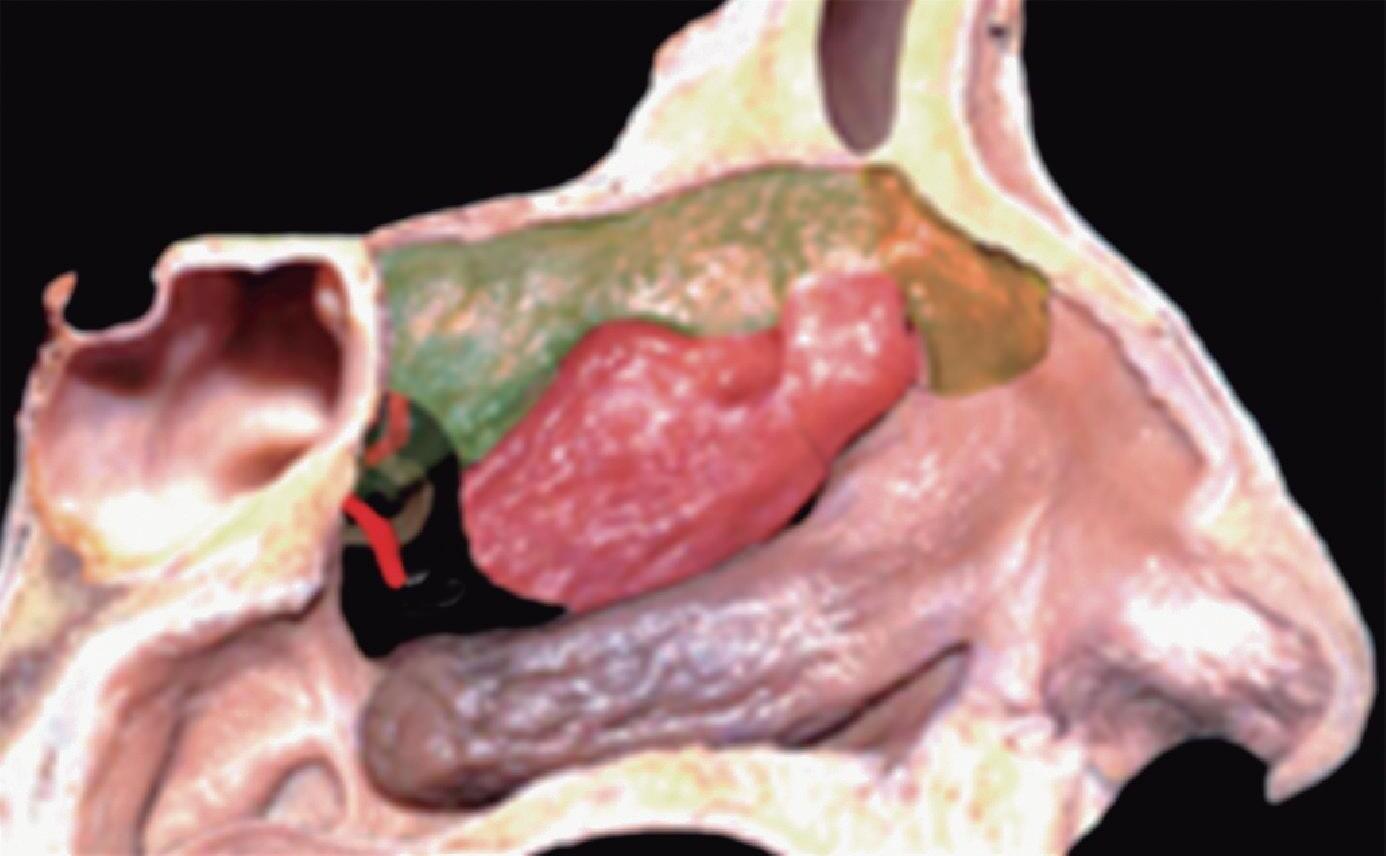

Fig. 1-20. Reconstrução tridimensional de TC demonstrando a lamela basal situada posteriormente à bulha etmoidal, acoplada à parede medial da órbita, fechando a câmara anterior: verde – concha média; vermelho – bulha etmoidal; amarelo – parede medial da órbita; lilás – processo uncinado.

Posterior à bulha etmoidal encontra-se a principal estrutura que fixa a concha média na órbita e na base do crânio: a lamela basal. Esta lamela, como a própria concha média, é oblíqua em relação à lâmina papirácea tanto no sentido anteroposterior como no superoinferior e delimita posteriormente a câmara anterior.

A bulha etmoidal lembra a forma de uma meia-lua e se encaixa na parede medial da órbita (lâmina papirácea) criando, posterossuperiormente (em sua relação com a porção vertical da lamela basal), um recesso algumas vezes chamado de seio lateral e outras de recesso suprabulhar, onde se abrem a própria bulha e cavidades etmoidais vizinhas.